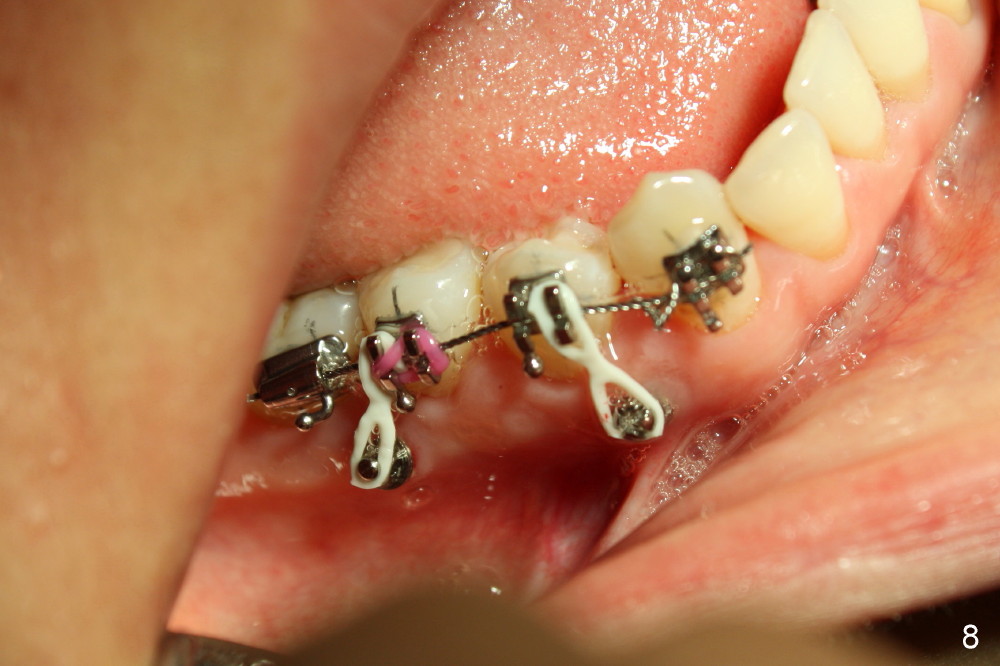

Power chains x 2 was added between the tooth #29 and posterior buccal mini-implant (Fig.8). The segmental wire is .0175 twisted one.